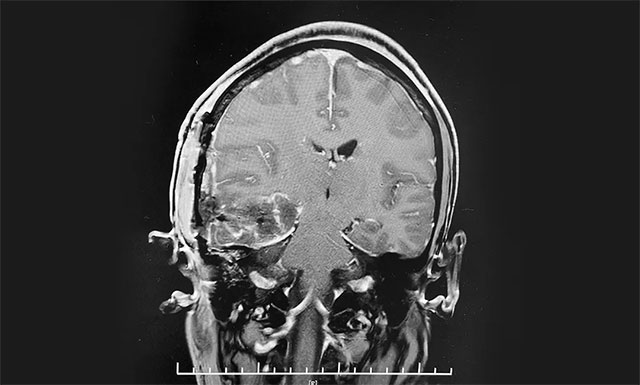

▲ 术后MR显示,“肿瘤”被切除